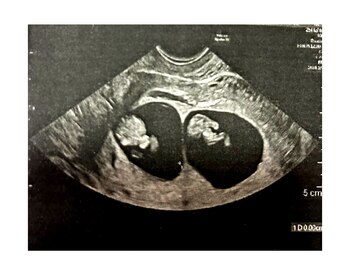

El 23 de octubre tenían turno para la primera ecografía. Fueron ilusionados. El médico exploró con el gel una y otra vez, meticulosamente, hasta que les tiró la bomba: “No es un bebé… son dos bebés”.

No podían creerlo. ¿Cómo dos? Sí, mellizos.

Beatrice estaba azorada, la posibilidad de mellizos en una familia en las que no hay casos es baja, pero les había tocado. Eran dos varones. La fecha prevista en la que, Nicolo y Leo, saldrán al mundo es el 20 de mayo próximo.